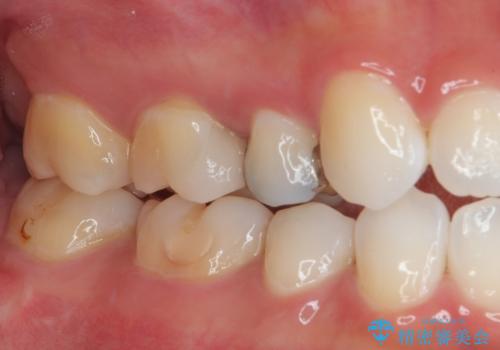

見た目、機能面共に大変喜んでいただきました。

歯と歯の間の虫歯をコンポジットレジンや保険のメタルインレーで治すと段差ができたりして清掃性が悪くなるので、セラミックインレー修復やゴールドインレー修復などの適合の良い詰め物で治療することをオススメします。